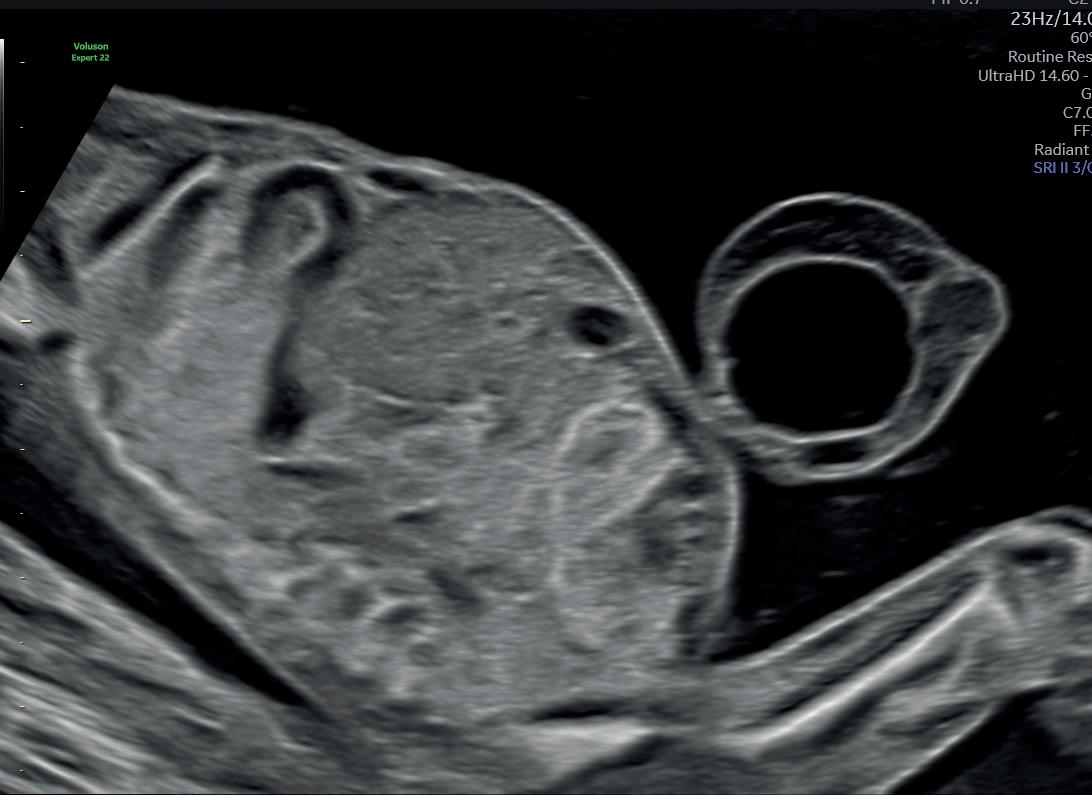

Η κατάψυξη ωάριων και η δυνατότητα γονιμοποίησής τους σε δεύτερο χρόνο επιτρέπει τη μετάθεση της τεκνοποίησης δυνητικά επ΄ αόριστον. Με τον τρόπο αυτό οι γυναίκες μπορούν να αποκτήσουν παιδί με δικά τους ωάρια όταν οι συνθήκες το επιτρέψουν. Οι γνώσεις που έχουμε αποκτήσει από τη διαχείριση γυναικών οι οποίες για ιατρικούς λόγους πρέπει να αναστείλουν την απόκτηση τέκνων, μας δίνουν τη δυνατότητα να εφαρμόσουμε αντίστοιχες τεχνικές σε γυναίκες που για κοινωνικούς ή επαγγελματικούς λόγους δεν επιθυμούν να κυοφορήσουν άμεσα. Η εξωγενής χορήγηση οιστρογόνων και προγεστερόνης και η δυνατότητα ορμονικής υποκατάστασης επιτρέπει την προετοιμασία της μήτρας για την εμφύτευση του εμβρύου ανεξάρτητα από την ηλικία της γυναίκας. Η τεχνογνωσία που εφαρμόζουμε σε γυναίκες με πρόωρη ωοθηκική ανεπάρκεια, μεταφέρεται σήμερα σε γυναίκες που βρίσκονται ήδη σε εμμηνόπαυση. Τέλος η δυνατότητα παρακολούθησης της ανάπτυξης και του καλώς έχειν του εμβρύου και

η εξέλιξη των μονάδων εντατικής θεραπείας νεογνών επιτρέπουν τη βελτίωση της περιγεννητικής έκβασης σε περιπτώσεις που συμβαίνουν επιπλοκές της κύησης ή προϋπάρχει παθολογία της γυναίκας.

Τα παραπάνω επιστημονικά επιτεύγματα δημιουργούν τις προϋποθέσεις άρσης των αναπαραγωγικών ορίων που αιώνες τώρα είχαν τεθεί και έτσι ενισχύεται η γυναικεία αυτονομία. Σήμερα στη χώρα μας η εφαρμογή των μεθόδων υποβοηθούμενης αναπαραγωγής στις γυναίκες επιτρέπεται μέχρι τη συμπλήρωση του 54ου έτους.